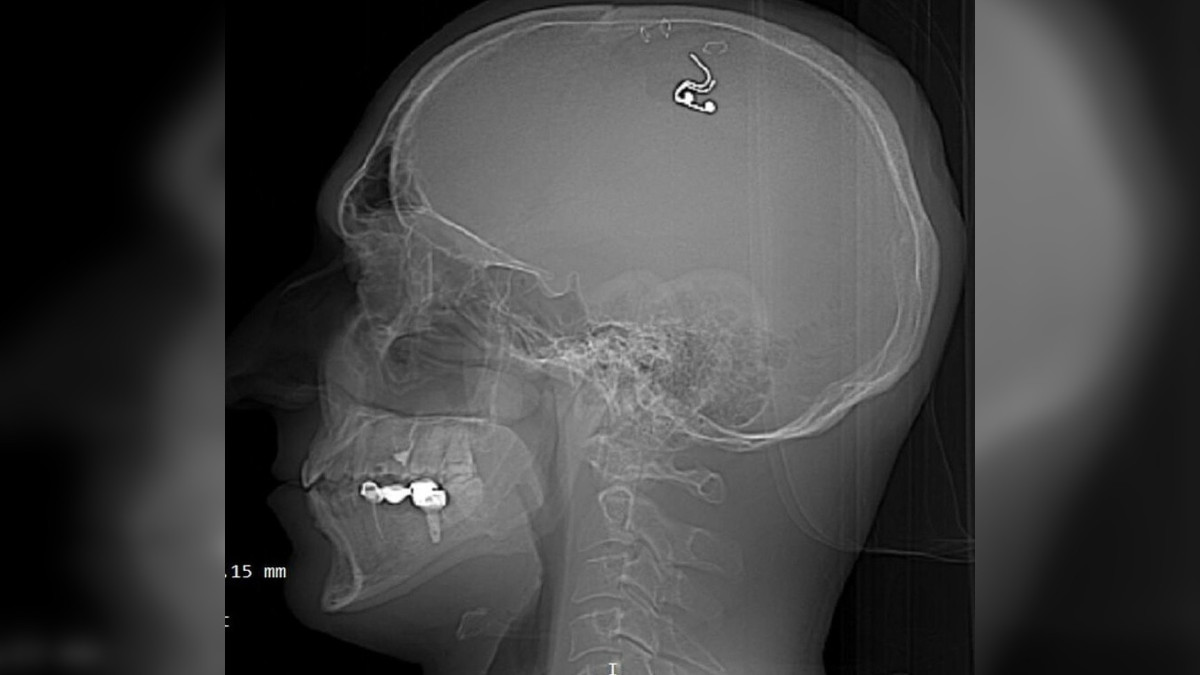

В Алматы мужчина просверлил себе череп и вставил чип, чтобы видеть осознанные сны

Мужчина родом из Новосибирска, сейчас проживающий в Алматы, решил экспериментировать с частями своего тела и вставил себе чип, просверлив череп дрелью. Об этом написал telegram-канал qumash_kz, передает ИА El.kz.

Как отмечает канал, интерес мужчины к этой необычной и опасной процедуре возник, когда он узнал о возможности видеть осознанные сны через такой чип. Изначально он рассматривал возможность обратиться к нейрохирургам для установки импланта, но отказался из-за опасений столкнуться с неприятными последствиями. Вместо этого, он посмотрел видео на YouTube и, практикуя на 5 овцах, решил провести операцию самостоятельно. Он смог успешно вживить чип и выжить.